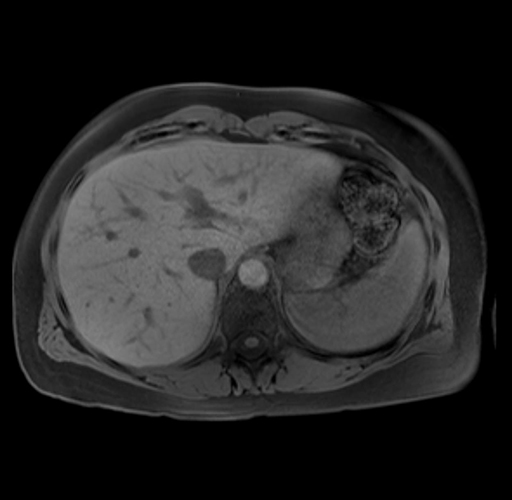

Imaging Analysis

Look through the patient's CT scan to identify any areas of concern for the necessary procedure.

Based on your CT findings, which issue(s) are present and would give reason for "planned slowing down moment(s)" in this case?